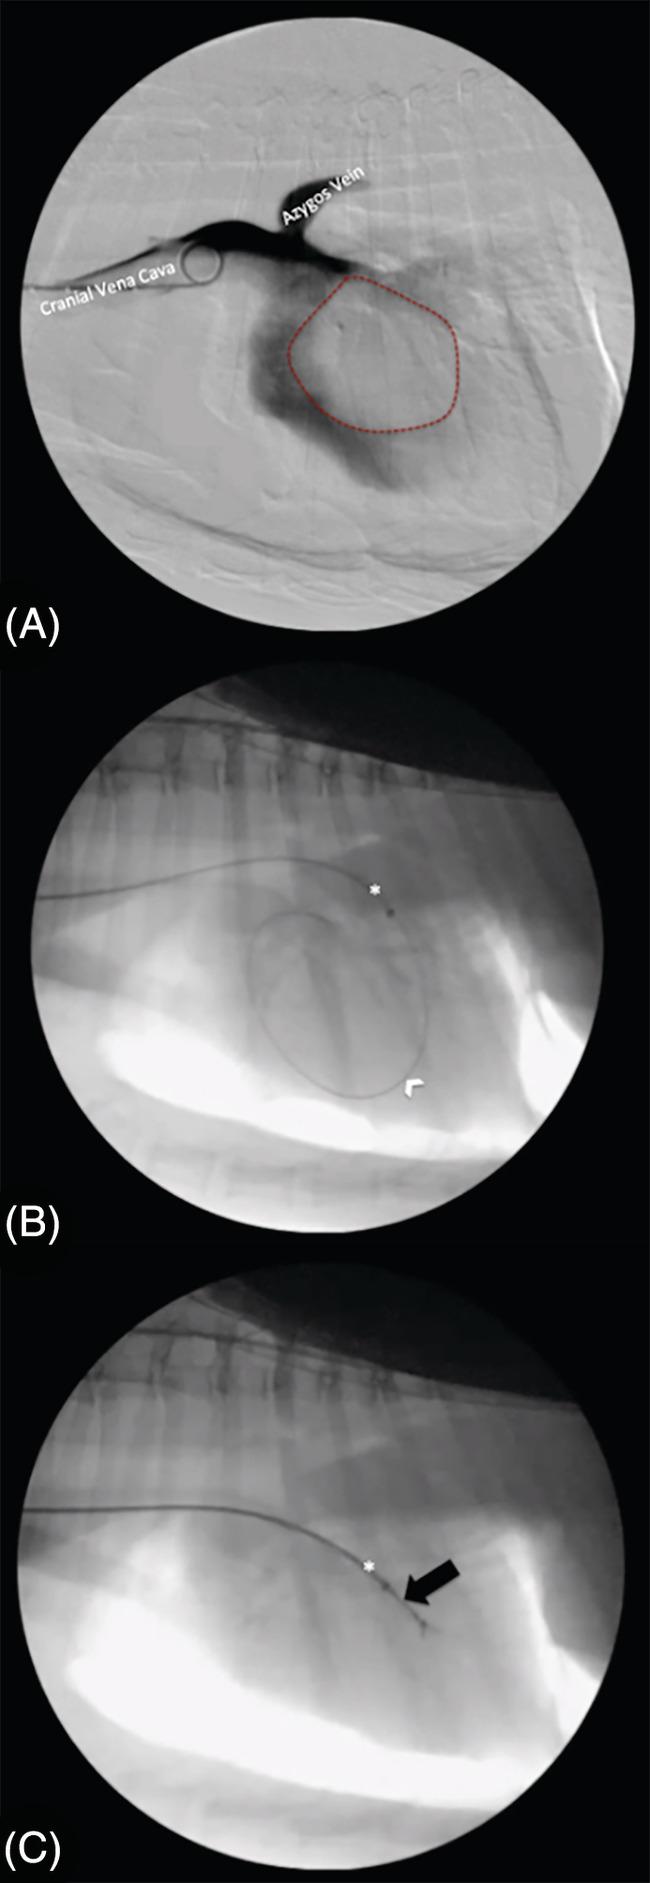

Biopsy of an intracardiac paraganglioma in a dog using a fluoroscopically guided endovascular technique.

A 10-year-old female spayed mixed breed dog was evaluated for diarrhea and vomiting. Diagnostic imaging demonstrated the presence of an intracardiac mass. A modified Seldinger technique was used to access the right jugular vein, and an endomyocardial biopsy forceps was introduced through a sheath to obtain several biopsies. Histopathology and immunohistochemistry demonstrated a paraganglioma. The dog underwent 1 fraction of radiotherapy and l-asparaginase chemotherapy and was discharged. The dog developed a pulmonary thromboembolism 2 days after radiotherapy and chemotherapy, and the owner elected humane euthanasia. Although long-term assessment of treatment response was unable to be performed, this novel diagnostic option could be considered for similar cases due to success in obtaining a histopathologic diagnosis, which is essential in developing a disease-specific treatment plan. This report also describes the use of radiotherapy for primary treatment of an intracardiac neoplasm, which can be a consideration in the future.